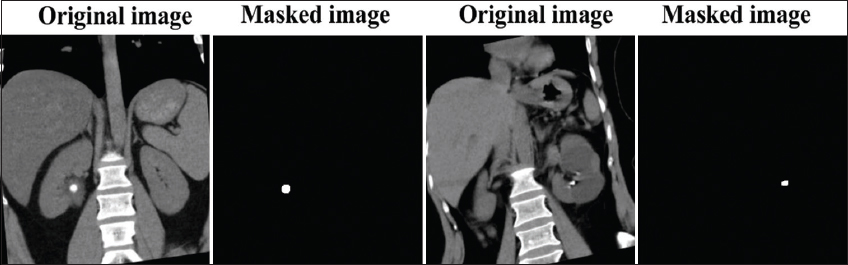

Furthermore, the study utilized the publicly accessible Kidney Stone Segmentation Dataset from Kaggle (https://www.kaggle.com/datasets/bemorekgg/kidney-stone-segmentation-dataset) to train and assess the efficacy of the suggested segmentation algorithm. This dataset includes CT scans of kidney stones together with related segmentation masks developed by the Segment Anything Model (SAM) utilizing YOLO bounding box annotations. The CT images are supplied in Joint Photographic Experts Group (JPEG) format, while the segmentation masks are presented as binary Portable Network Graphics (PNG) images. The dataset consists of 923 image-mask pairings, randomly assigned to training (70%, 646 images + 218 rotated images), validation (20%, 184 images), and testing (10%, 93 images). Using the same model and evaluation subsets, Fig. 5 shows examples of Cagle images and masks.

thumblarge

Fig. 5. A sample dataset on kidney stones and masks is available on Kaggle.